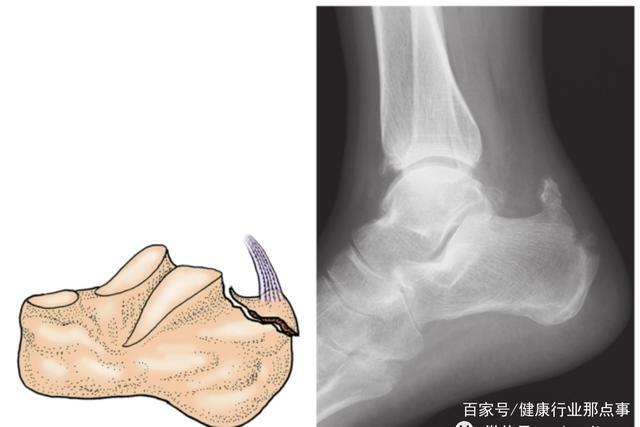

多图详解5种常见跟骨骨折分型